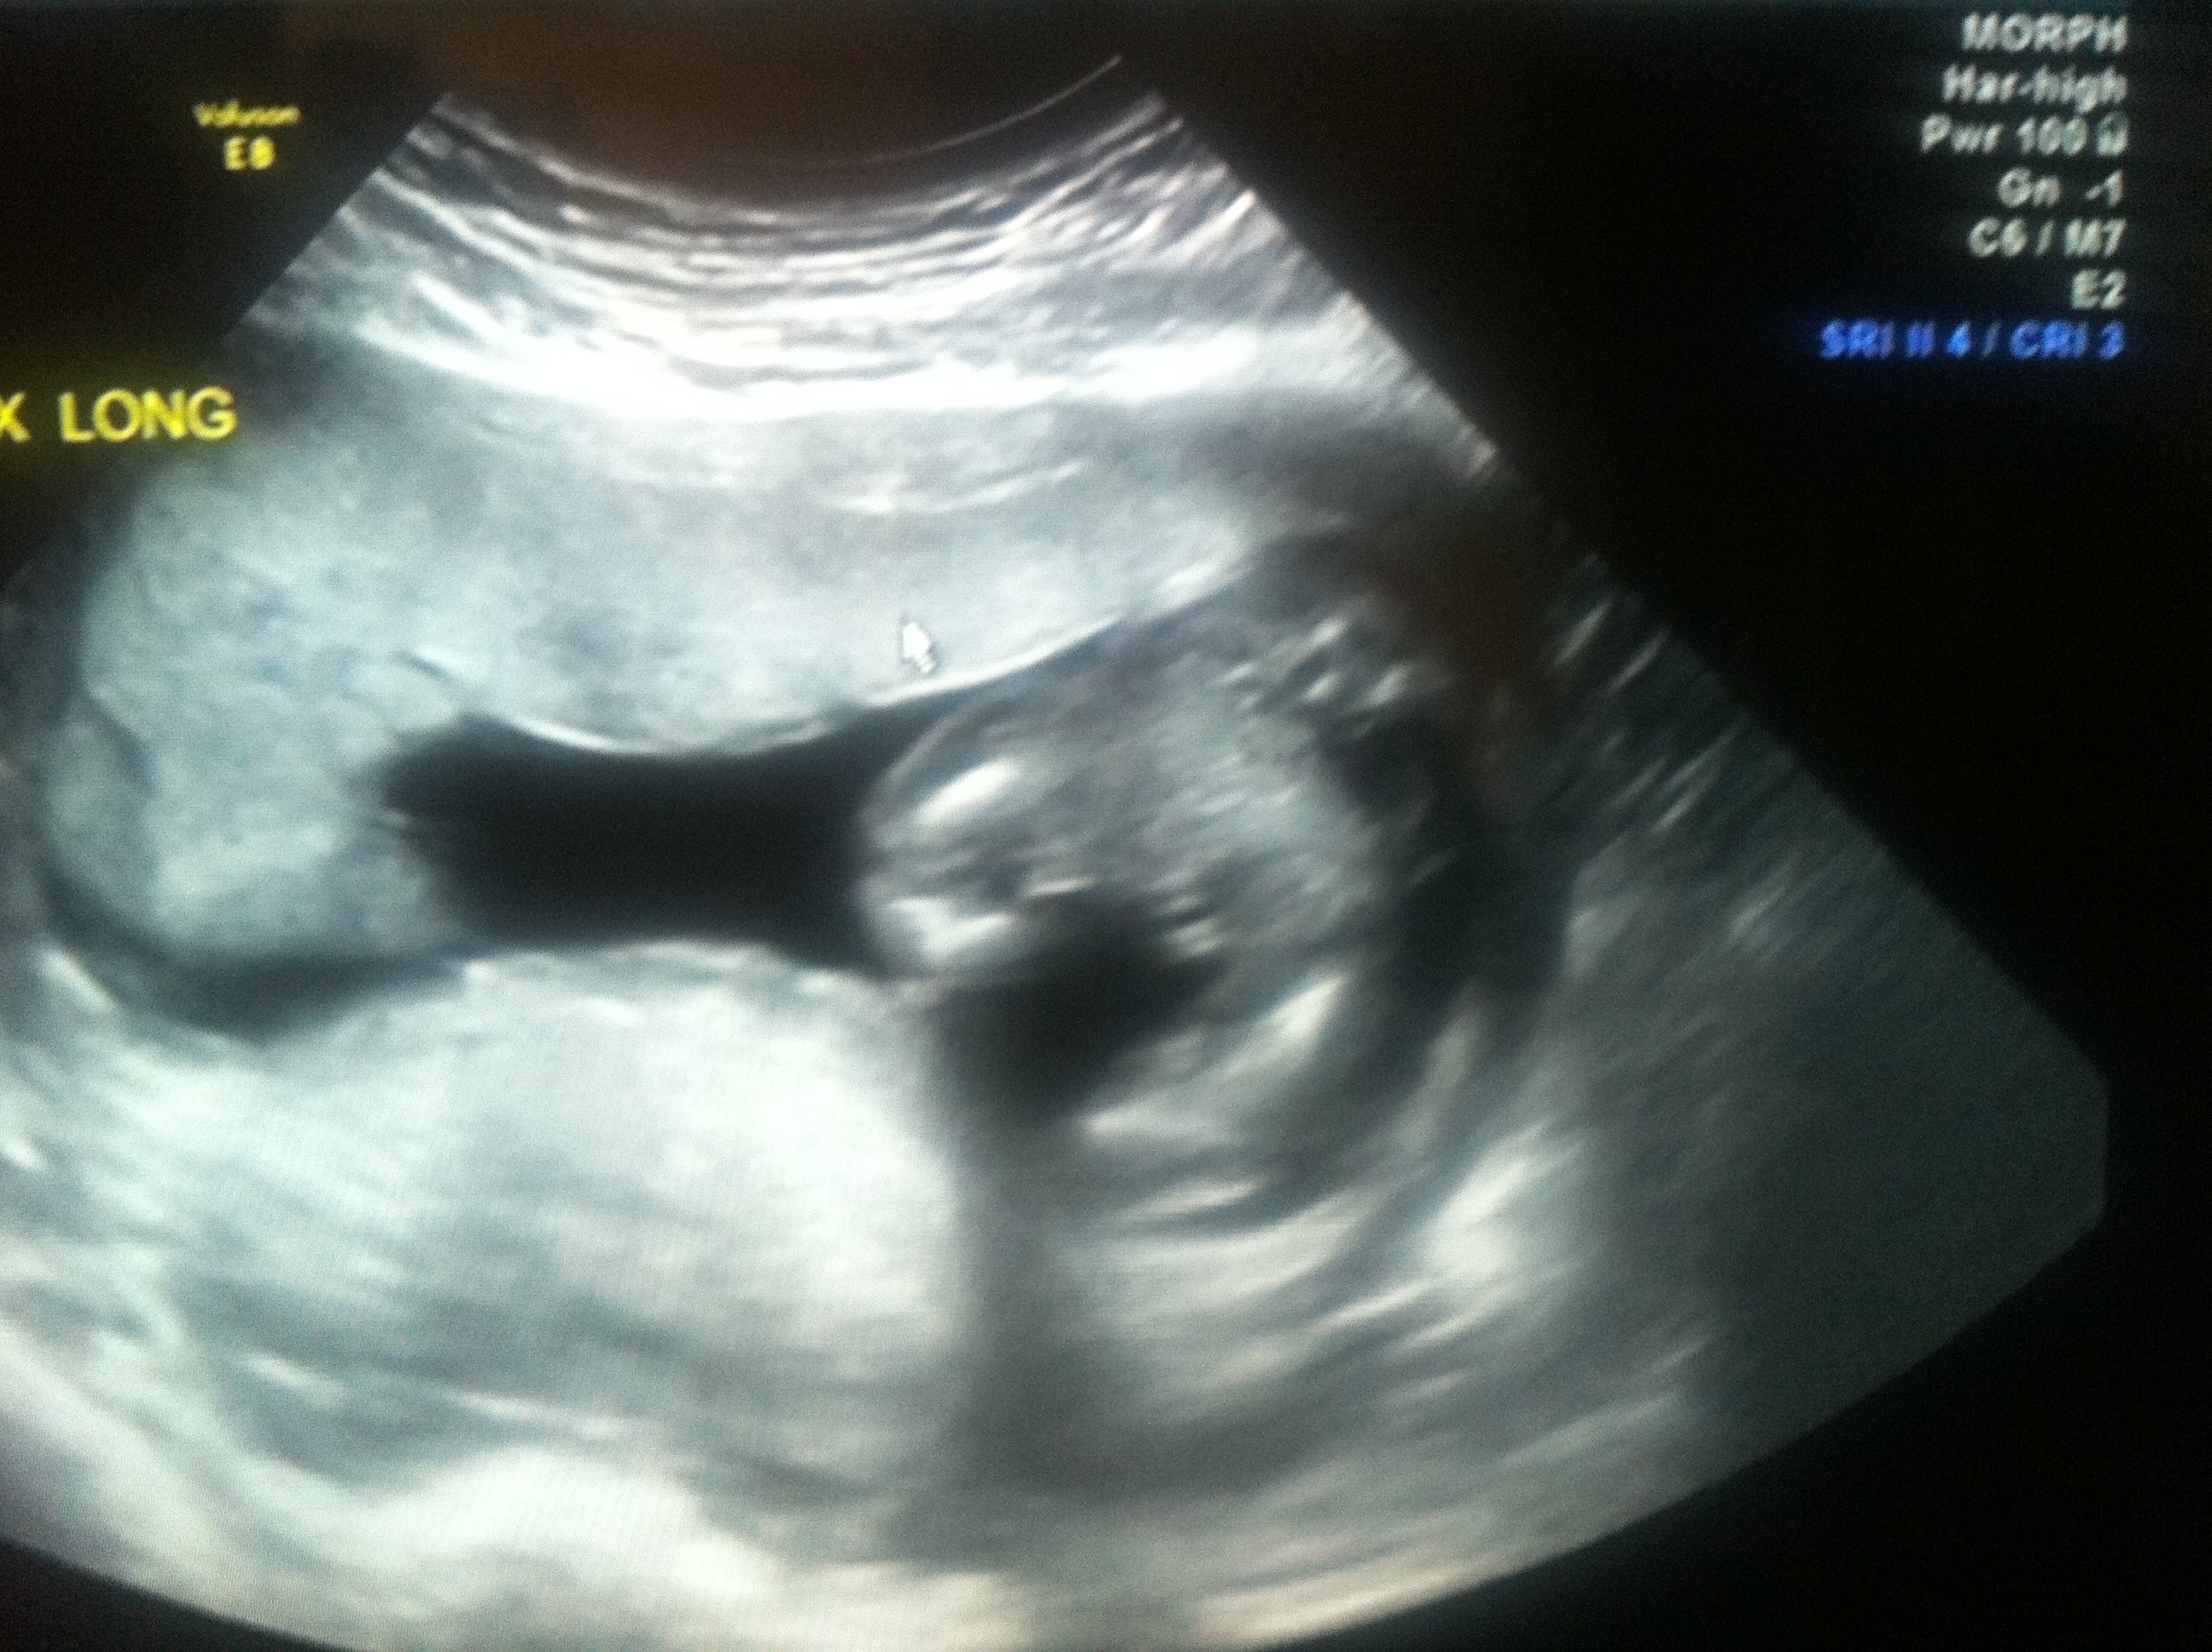

Looks like a girl!

She said no boy parts thinks girl, showed me 3labia lines then baby was real uncooperative and she started doubting herself lol

Looks like a girl! Congrats!

I didn't know what I was looking at with that first shot but the following ones are ALL girl. Congrats!